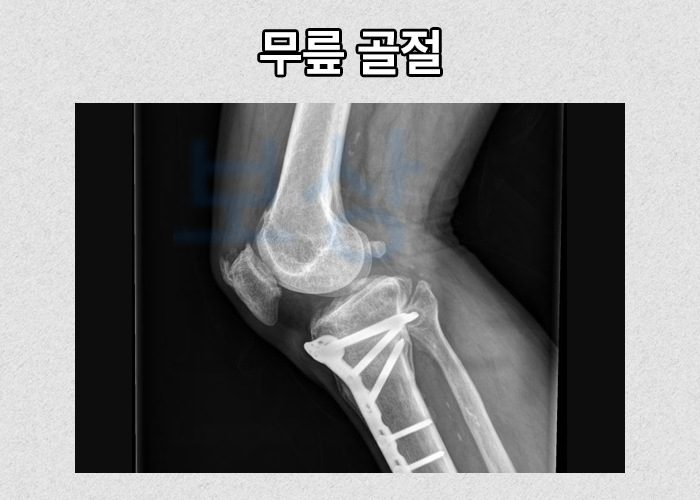

상해나 교통사고와 같은 외상성 요인으로 무릎이 손상되어 인공관절 치환술을 진행하실 수 밖에 없는 경우가 있습니다.

그런 경우에는 내가 가입해둔 보험에서 일반 상해후유장해 보험담보에서 장해 보상도 받으실 수 있습니다. 주로 기본계약이나 주계약에 일반상해후유장해 담보가 포함되어 있는데요, 후유장해 보험금 청구는 의료 기관의 후유장해 평가를 받은 후유장해진단서를 필수로 제출하셔야 합니다.